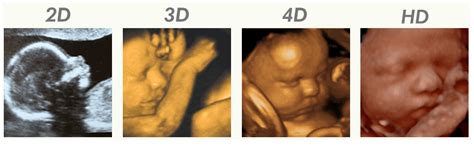

Naast medische echo’s, kunnen we middels een 2D en 3D/4D pretecho een mooie herinnering maken. Bent u nieuwsgierig naar het geslacht van uw kindje of wilt u zien hoe het zich beweegt in de buik? Maak dan een afspraak bij Puur Verloskundig Centrum Veldhoven. Vanaf 6 weken zwangerschap kunt u de ontwikkeling van uw kindje in de buik volgen.

Een 3D/4D pretecho wordt uit meerdere 2D beelden opgebouwd.